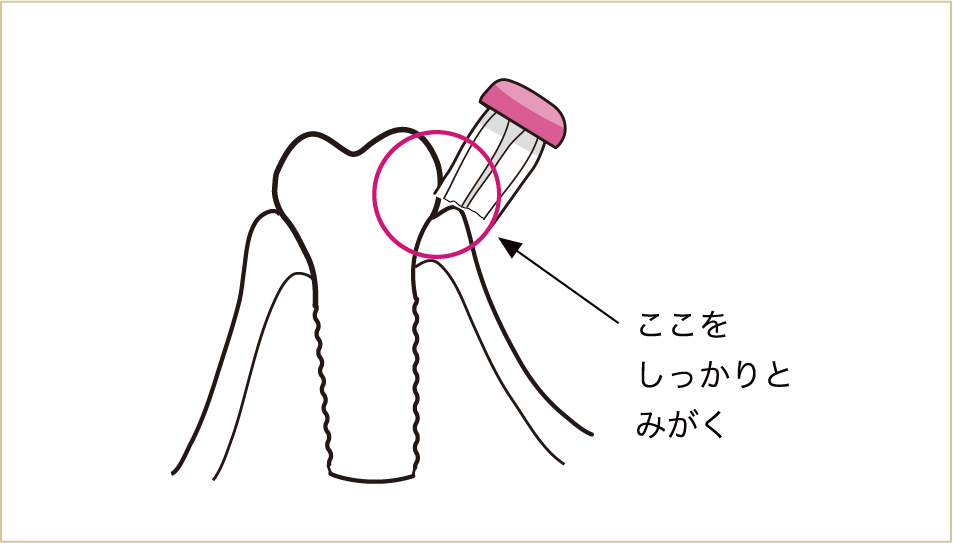

インプラント周囲で、特にブラッシングに注意してほしい所があります。

したがって、インプラントの周囲では、歯と歯肉の境目、特に歯肉の中へ歯ブラシの毛先を入れる感覚がより大切になります。

インプラントの連結部はワンタフトブラシなどで良くみがく。歯医者で歯科衛生士に、特殊なブラシの使い方をしっかりと教わることも重要なポイント。